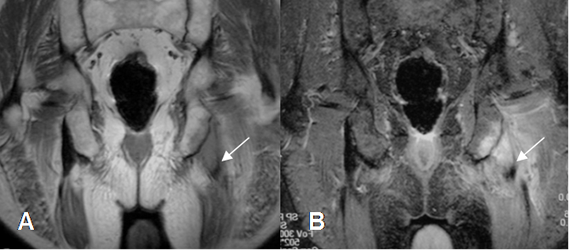

Las avulsiones son detectadas generalmente con Rx, pero puede necesitarse estudio comparativo o complemento con TAC y RM en algunos casos dudosos. (14). (Fig 77 y 78).

Fig 78. Avulsión.

A: RM coronal en T1 y B: RM coronal en STIR. Cambios inflamatorios sobre la tuberosidad isquiática izquierda por avulsión. Hay retracción en el origen de los isquiotibiales.